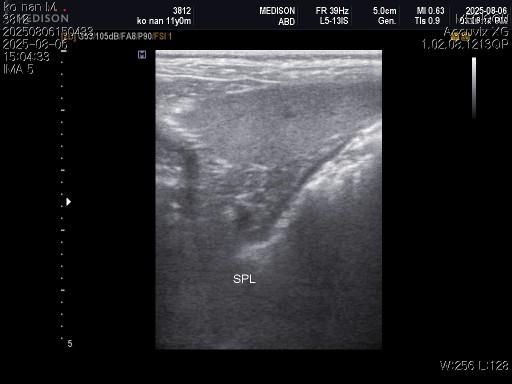

1) 혈액검사와 엑스레이 그리고 초음파상 혈뇨의 원인이 나타나지가 않는지 궁금합니다.

3) 신장결석이 어느정도인지도 궁금합니다.

4) 양쪽 부신의 크기가 궁금합니다.